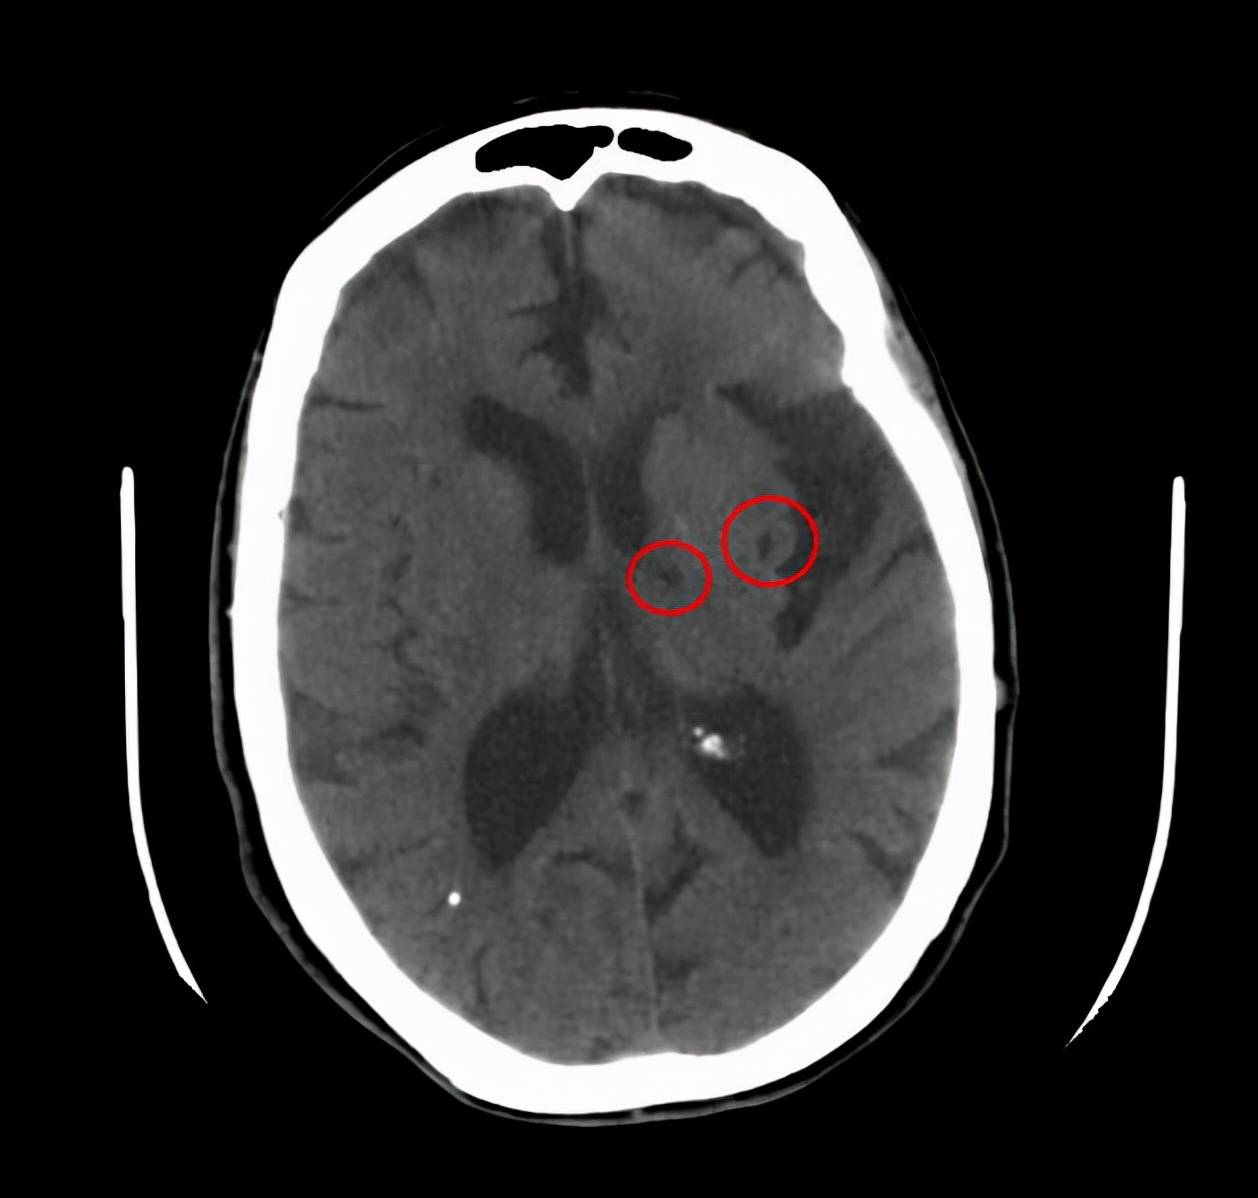

其实腔梗只是一个缩写 , 它的全名是腔隙性脑梗死 , 这种脑梗死的本质 , 其实是大脑血管中小动脉的闭塞而出现的脑组织损伤 。

一般来说范围在1.5厘米-2厘米之间 , 这个范围 , 我们都称之为腔隙性脑梗死 。

特别是在之后复查的影像学检查中 , 比如CT和核磁当中可以看到梗死之后的地方成为了一个天然的腔隙 , 所以因此得名腔隙性脑梗死 。